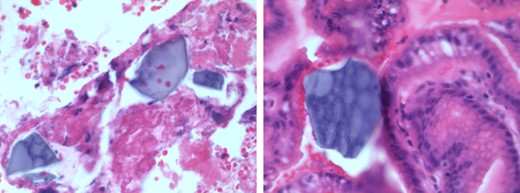

The resected gastric edges of the perforation site were sent for pathological examination, which revealed the presence of fibrinoleukocytic debris with rhomboid, birefringent crystals, suggestive of Kayexalate in the gastric wall (Fig. 1).

Foci of serositis and fibrinoleukocytic debris with rhomboid, birefringent crystals, suggestive of Kayexalate, in the gastric wall.